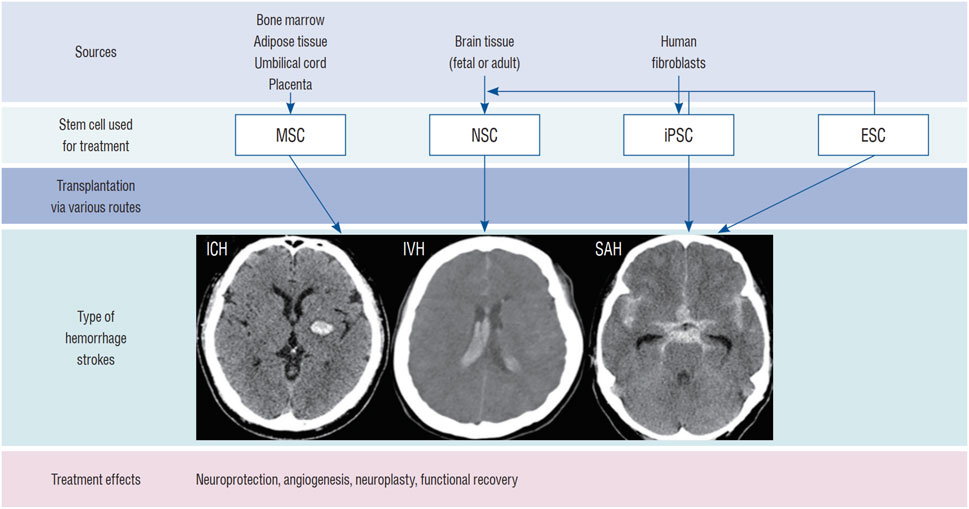

推進(jìn)腦出血的干細(xì)胞治療需要整合生物材料、基因工程和預(yù)處理策略以提升療效。盡管前景看好,但目前仍缺乏大規(guī)模、設(shè)計(jì)嚴(yán)謹(jǐn)?shù)哪X出血臨床試驗(yàn)和長(zhǎng)期安全數(shù)據(jù)(圖3)。未來(lái)研究需著重優(yōu)化給藥途徑、劑量、時(shí)機(jī)以及符合藥品生產(chǎn)質(zhì)量管理規(guī)范的大規(guī)模細(xì)胞制備工藝。

圖3:用于治療ICH的干細(xì)胞類(lèi)型:該圖顯示了用于治療ICH(腦實(shí)質(zhì)出血、腦室內(nèi)出血[IVH]和蛛網(wǎng)膜下腔出血[SAH])的干細(xì)胞類(lèi)型,包括 NSC、間充質(zhì)干細(xì)胞 (MSC)、誘導(dǎo)多能干細(xì)胞 (iPSC) 和胚胎干細(xì)胞 (ESC)。